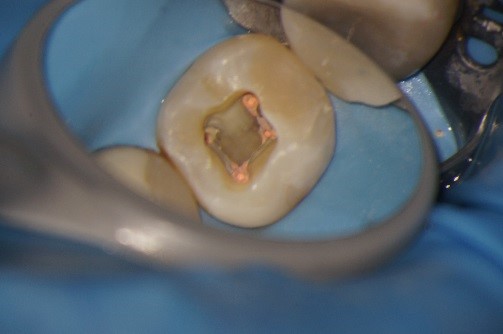

Hieronder ziet u de voortgang van een wortelkanaalbehandeling in zes foto’s..

Foto 4: De wortelkanalen zijn gevuld. De wortelkanaalbehandeling zelf is klaar. Alleen de vulling nog.